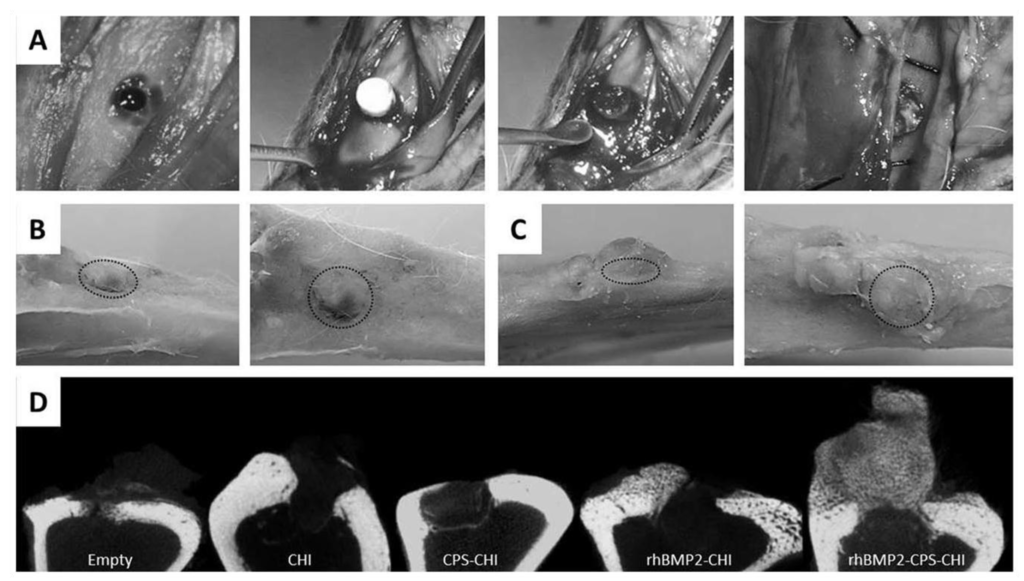

Recently, we have immobilized calcium phosphate salts (CPS) and bone morphogenetic protein 2 (BMP-2)—combined or alone—into chitosan scaffolds using ISISA process [35]. We analyzed whether the immobilized bone morphogenetic protein preserved its osteoinductive capability. We observed that rhBMP2 was not only released in a controlled fashion from CHI scaffolds but also preserved its osteoinductive character after release. Interestingly, we found that this multi-component scaffold exhibited a superior efficacy in bone regeneration than the scaffolds containing only one of the components, either CPS or rhBMP2, separately. This enhanced performance in both osteoconductive and osteoinductive terms opens the path to the future clinical application of these materials in dental surgery and, more specifically, in maxillary sinus augmentation procedure. In this procedure, large area of the maxillary sinus are lifted and replaced with bone, which serves to support future implant placement. It is worth noting that the filling material most used nowadays is porous resorbable hydroxyapatite, which is osteoconductive but not osteoinductive as the rhBMP2-CPS-CHI scaffolds described in this work (Figure 5).

Figure 5. Surgery (A), gross morphology after euthanasia (B,C) and microCT analysis of samples (D). Surgery images (A) show scaffold implantation process. After euthanasia gross morphology images were obtained at different angles (B,C) (Dotted circle indicates defect location).Defect area was still observed in CPS-CHI implanted tibias (B), while in rhBMP2-CPS-CHI implanted tibias high amount of newly-formed hard tissue, apparently bone, appeared vertically from the defect (C). MicroCT study (D) confirmed trabecular bone formation in rhBMP2-CPS-CHI implanted tibias, while it seemed no scaffold-resorption in any case. Neither seemed a robust new bone formation in the rest of implanted scaffolds compared to empty controls. Reprinted with permission from [35]. 2014 PLoS One. Creative Commons License.